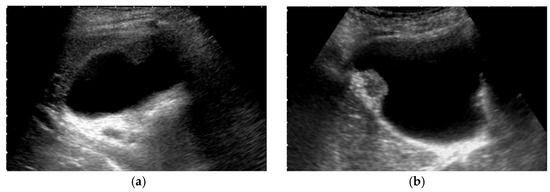

Figure 2. Evaluation of GB using a HRUS technique. Compared with an image of routine US (a), localized slight thickening of an inner hypoechoic layer was clearly shown in the magnified image using a high-frequency transducer (b) (GBC case).